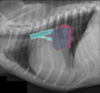

What sign of left atrial enlargement in cats is shown in this image?

left: normal right: widening of cranial aspect of heart due to "baggy" left atrium